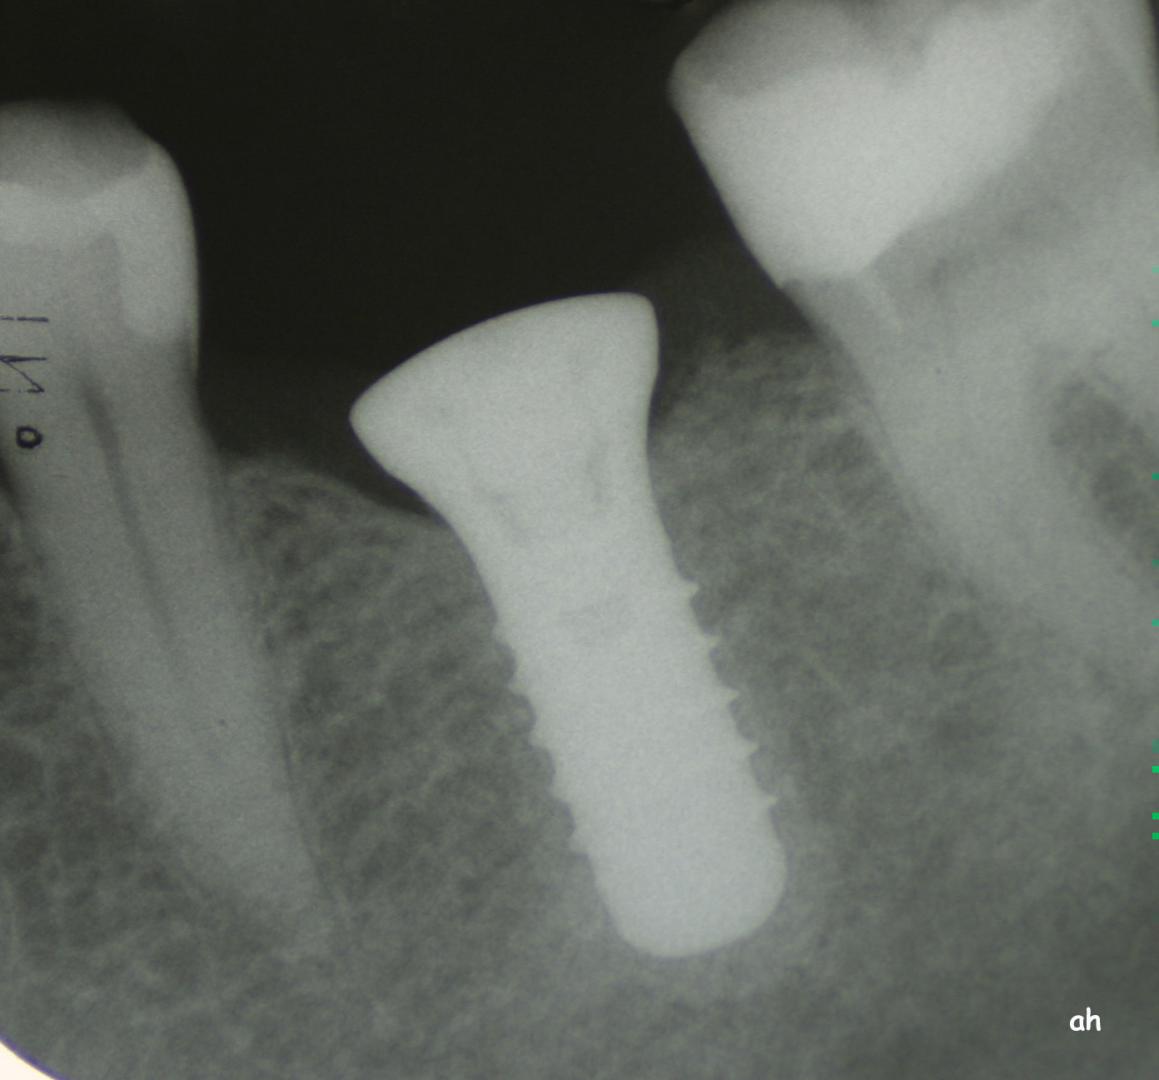

Exemple 7: Un implant au niveau de la deuxième prémolaire inférieure gauche.

Exemple 7: Le moignon vissé sur l'implant.